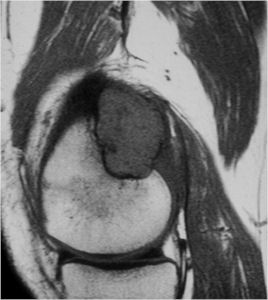

MRI:

- Also useful in determining extent

- There is often extensive edema around the tumor in the surrounding bone and soft tissues that can lead to a misdiagnosis of a malignant tumor.